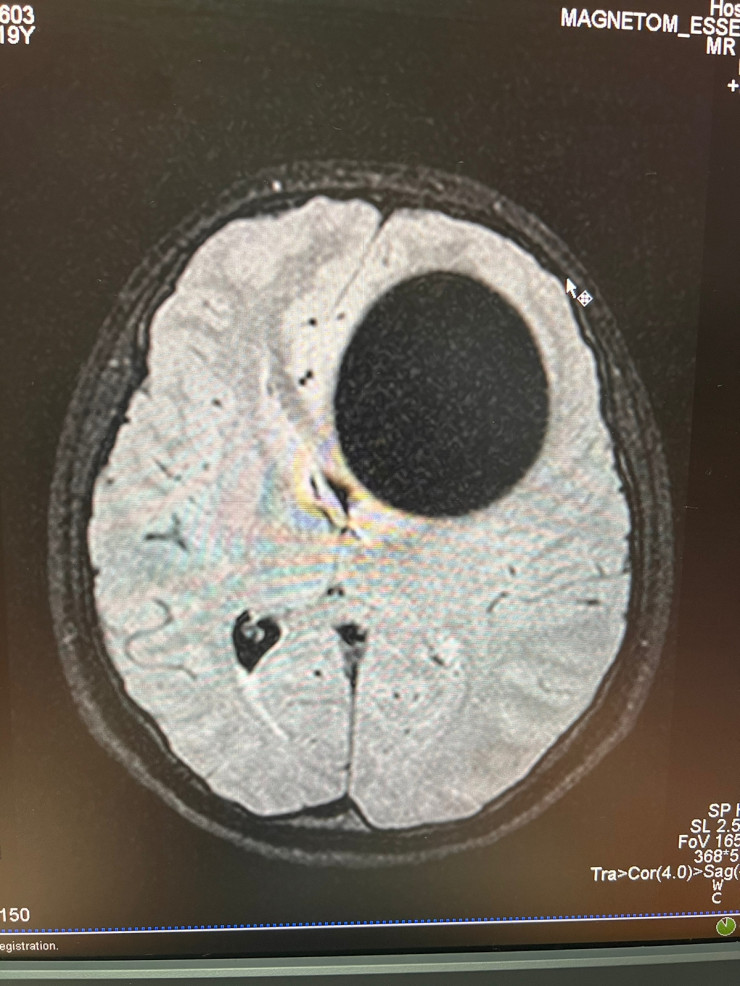

20-летняя пациентка поступила 17 января к невропатологам больницы скорой медицинской помощи (БСМП) Семея. Сначала у нее подозревали инсульт, однако на компьютерной томографии в головном мозге была выявлена огромная киста диаметром 5,5 сантиметра.

Эхинококковая киста диаметром 5,5 сантиметра. Материал предоставлен общественным объединением KAZNEURO

"Пациентка поступила с жалобами на выраженную головную боль, головокружение, тошноту, рвоту, общую слабость, заторможенность. Она не могла ходить. Ей было сделано дополнительное обследование - МРТ головного мозга. За короткое время был установлен диагноз "эхинококкоз" и принято решение о трепанации черепа и извлечении опухоли. Незамедлительно она была прооперирована. Пациентке экстренно удалили эхинококк из головного мозга", - сообщили нейрохирурги БСМП города Семея.

Так выглядит эхинококковая киста головного мозга. Материал предоставлен общественным объединением KAZNEURO